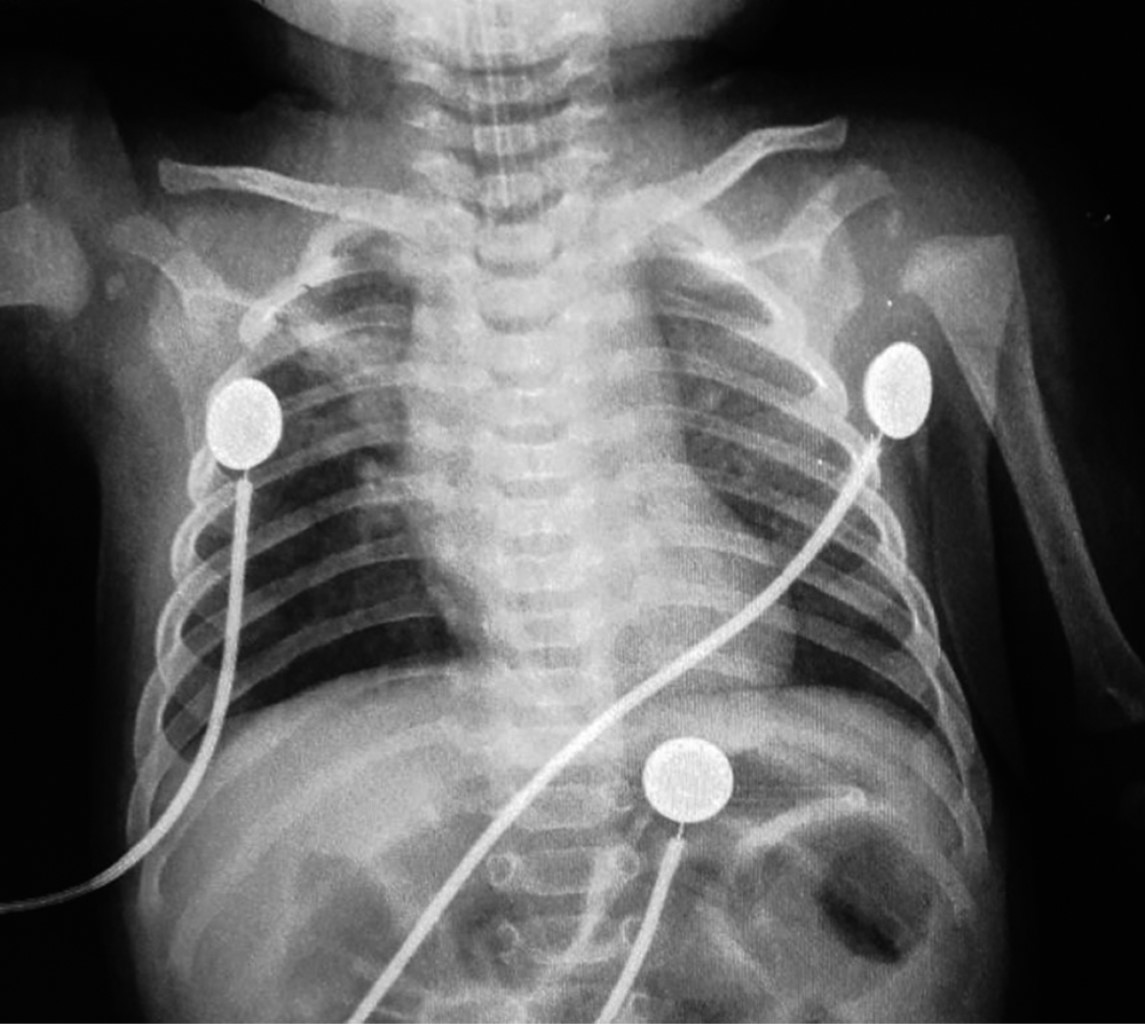

Radiografía de tórax con presencia de infiltrado grueso diseminado (Figura 1).

Figura 1